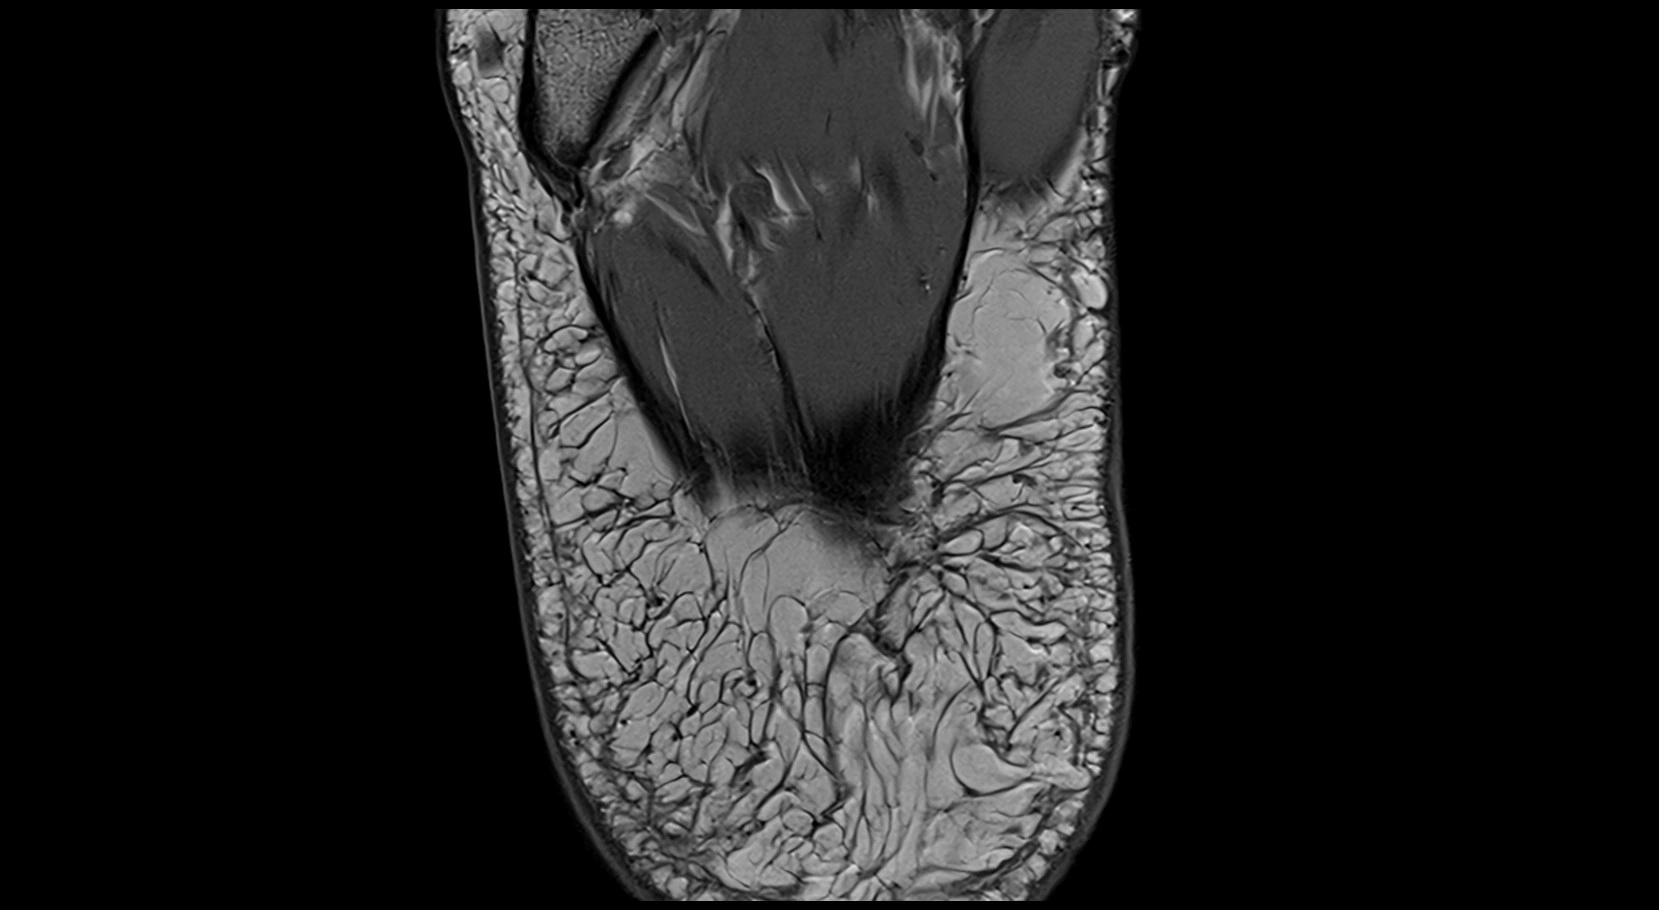

MRI image

image